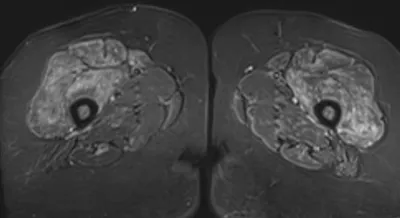

This collection contains 1 radiology images related to muscle oedema, including various imaging modalities such as X-rays, MRIs, CT scans, and ultrasound images commonly used in medical diagnosis and education.